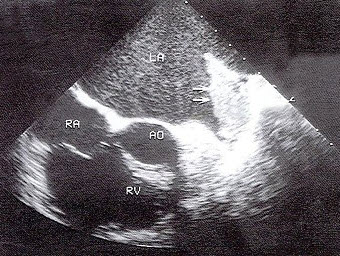

5、单项选择题

如图,初步超声诊断为()

A.二尖瓣返流

B.三尖瓣返流

C.主动脉瓣返流

D.肺动脉瓣返流

E.以上均不是